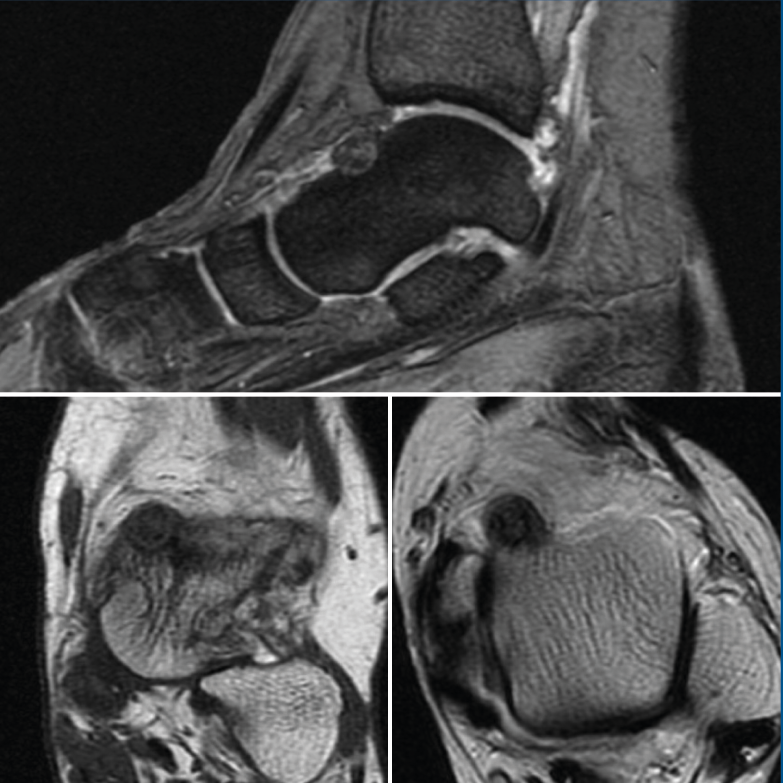

Figura 2. Resonancia magnética nuclear inicial que presenta una tumoración ósea en el cuello del astrágalo con cambios inflamatorios periféricos y abundante edema óseo difuso, sugestivo de osteoma osteoide.

Se trata de una mujer de 64 años que presenta dolor en el tobillo izquierdo de 36 meses de evolución; la paciente refiere un dolor nocturno para el que precisa toma de salicilatos. Se realizó una radiografía que no evidenció lesiones óseas, la TAC nos informa de una lesión lítica yuxtacortical en el astrágalo de 8 mm de diámetro con calcificaciones de aspecto condroide en el centro de la misma (Figura 1). La RMN sugería un OO, ya que presentaba una tumoración ósea en el cuello del astrágalo con cambios inflamatorios periféricos y abundante edema óseo difuso del astrágalo (Figura 2).